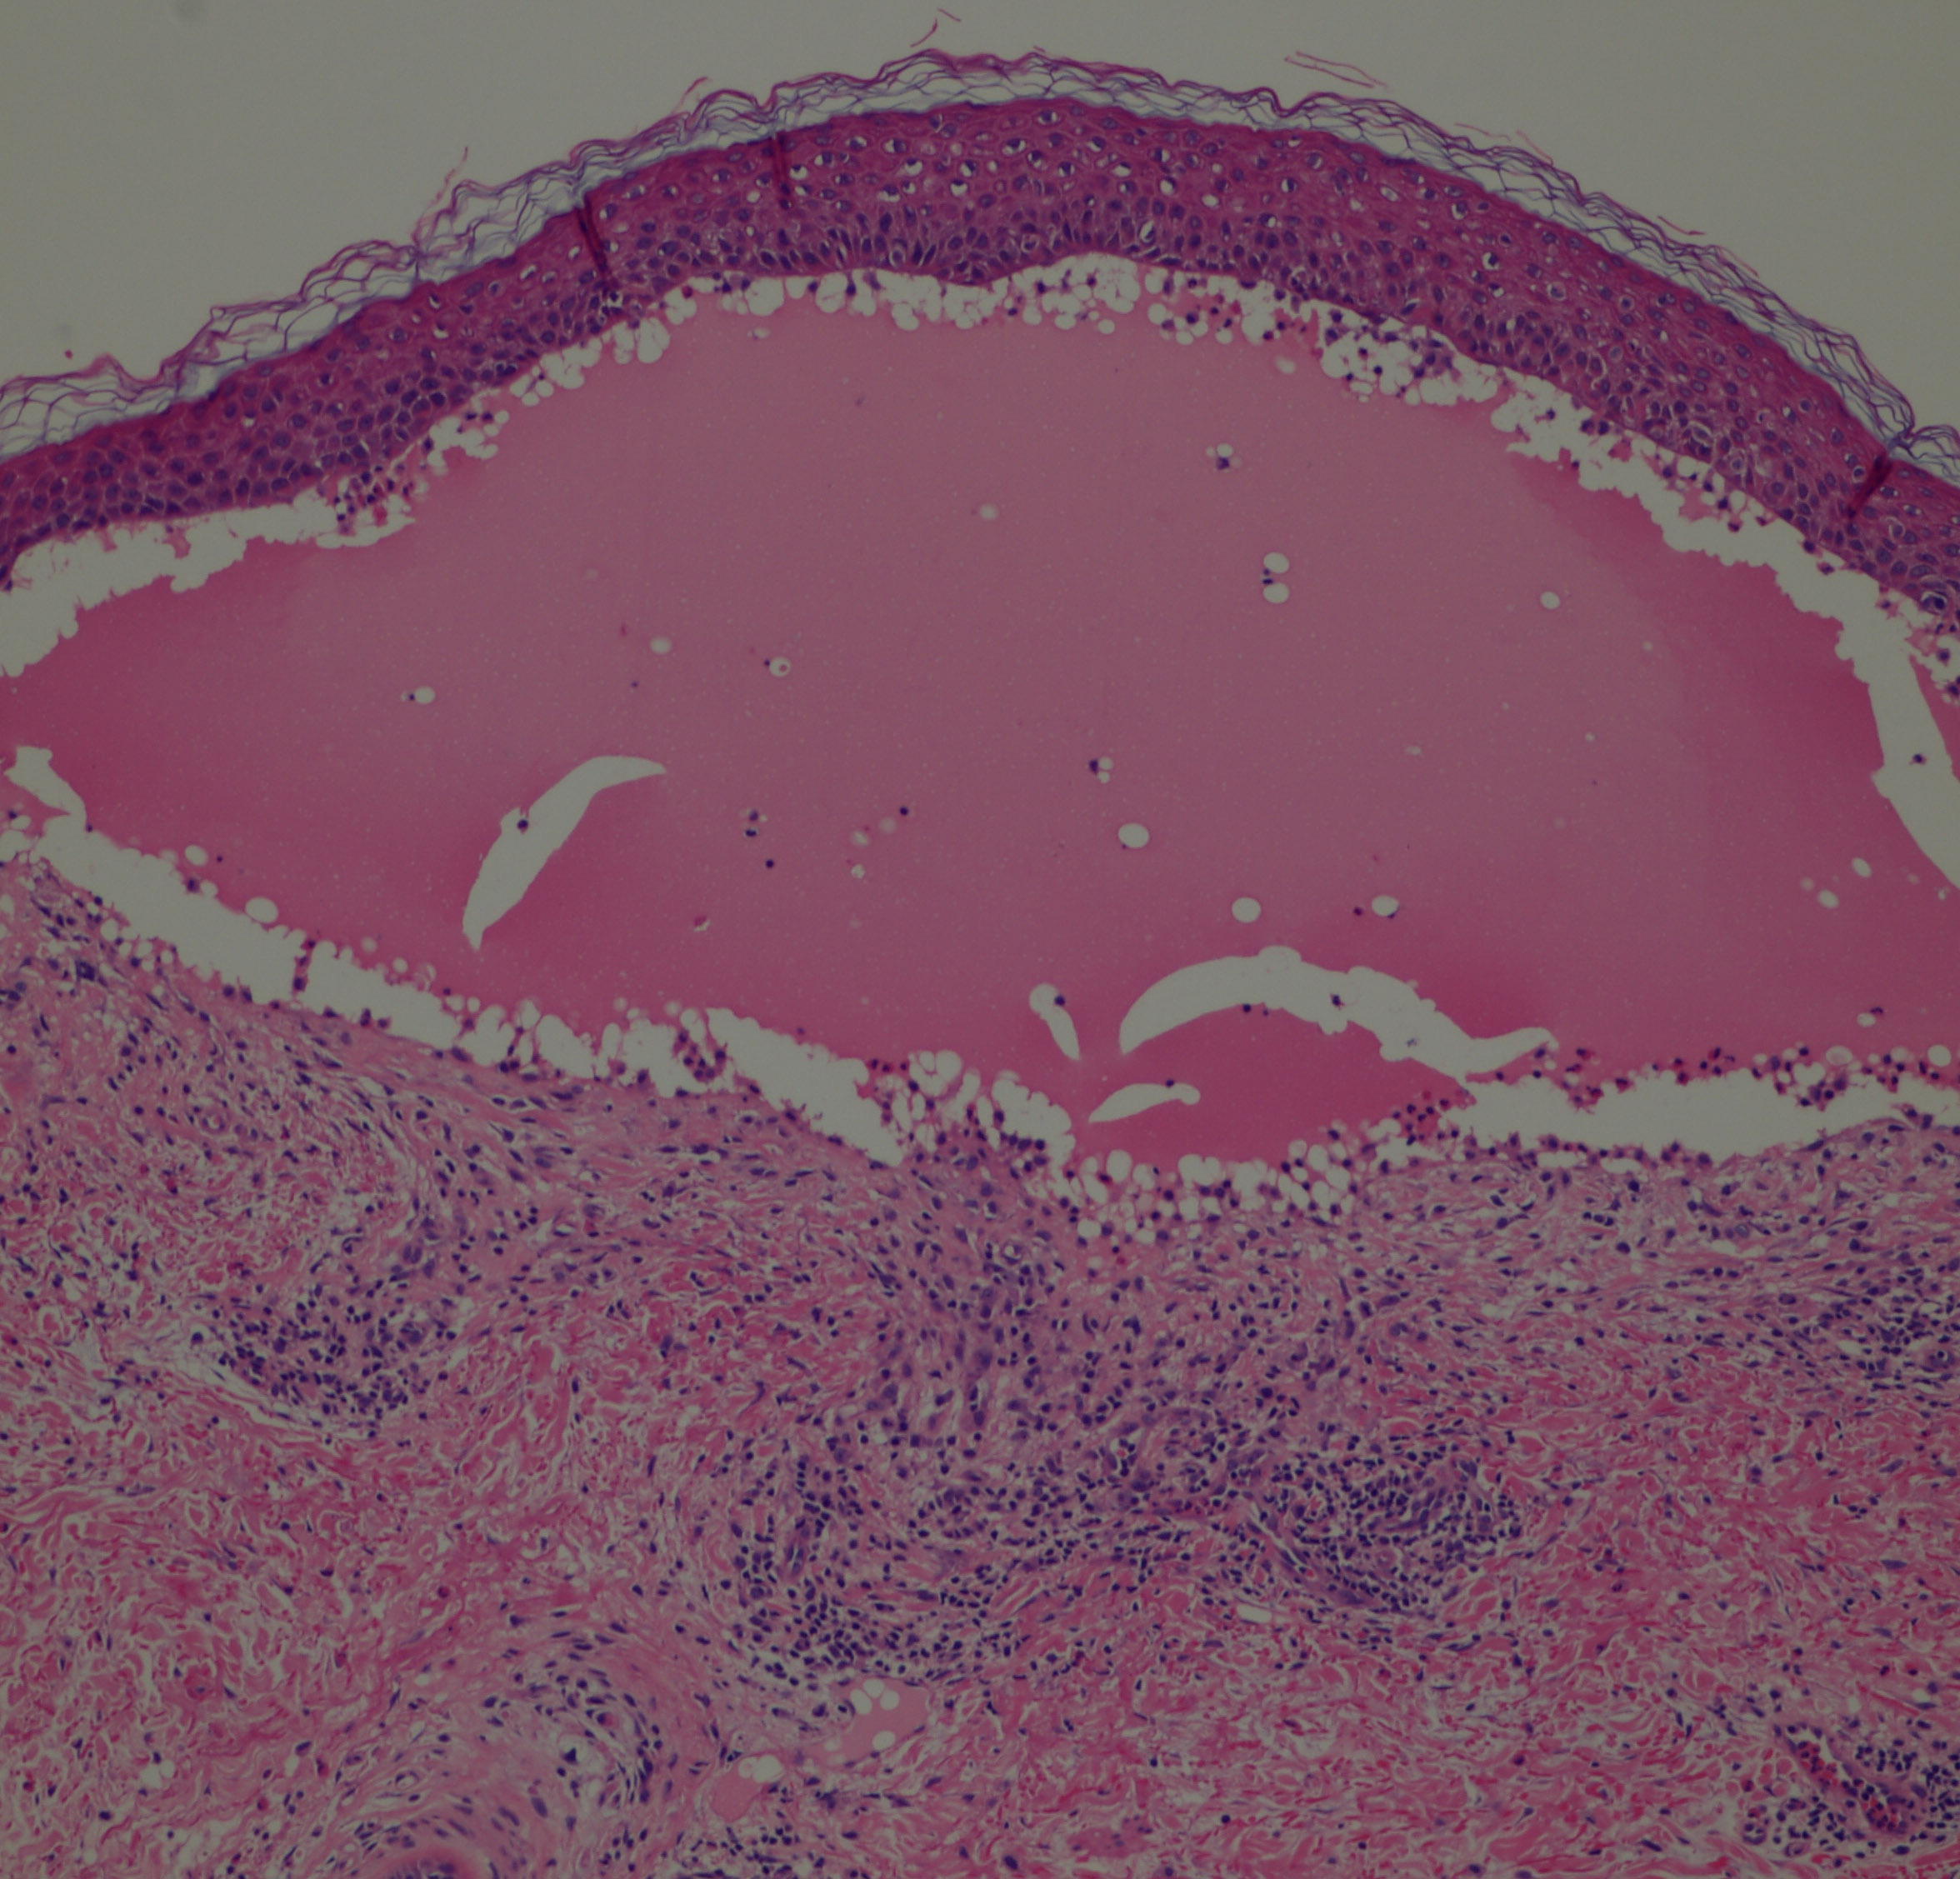

In early lesions, papillary dermal edema in combination with a cell-poor or cell-rich perivascular lymphocytic and eosinophilic infiltrate is present. The blister arises at the dermal-epidermal junction . In the cell-rich pattern, which correlates clinically with blisters arising on erythematous skin , eosinophilic papillary abscesses may develop with numerous perivascular and interstitial eosinophils intermingled with lymphocytes and neutrophils in the superficial and deep dermis. Early lesions may have the histologic features of eosinophilic cellulitis (Well’s syndrome). Eosinophilic spongiosis may occur. The cell-poor pattem is observed

when blisters develop on relatively normal skin , in which there is usually a scant perivascular lymphocytic infiltrate with few eosinophils, some scattered throughout the dermis and others near the epidermis. The blister contains few inflammatory cells. Epithelial migration and regeneration may result in an intraepidermal split in older blisters. Similar to pemphigus vegetans, a hyperplasia of the epidermis, subepidermal bullae, and accumulations of eosinophils and lymphocytes may be seen.

IF Testing. DIF testing of perilesional skin has shown linear C3 deposition  at the dermal-epidermal junction in virtually 100% of cases and IgG in 65% to 95%. IIF studies reveal circulating anti­basement membrane zone IgG antibodies in 70% to 80%. Similarly deposited IgA and IgM are observed in about 25% of cases. No correlation exists between the antibody titer and the clinical severity of the disease. The IgG is located within the lamina lucida, where it appears to be bound specifically to the hemidesmosomes.